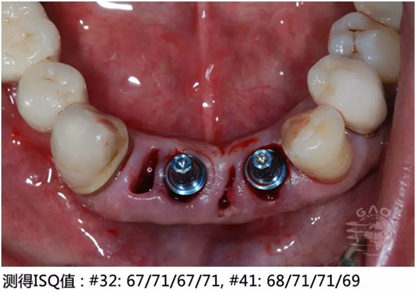

[臨床分享]使用取帽印模工具盒進(jìn)行下頜前牙區(qū)修復(fù) 科貿(mào)嘉友口腔收錄

- [臨床分享]使用取帽印模工具盒進(jìn)行下頜前牙區(qū)修復(fù) 科貿(mào)嘉友口腔收錄